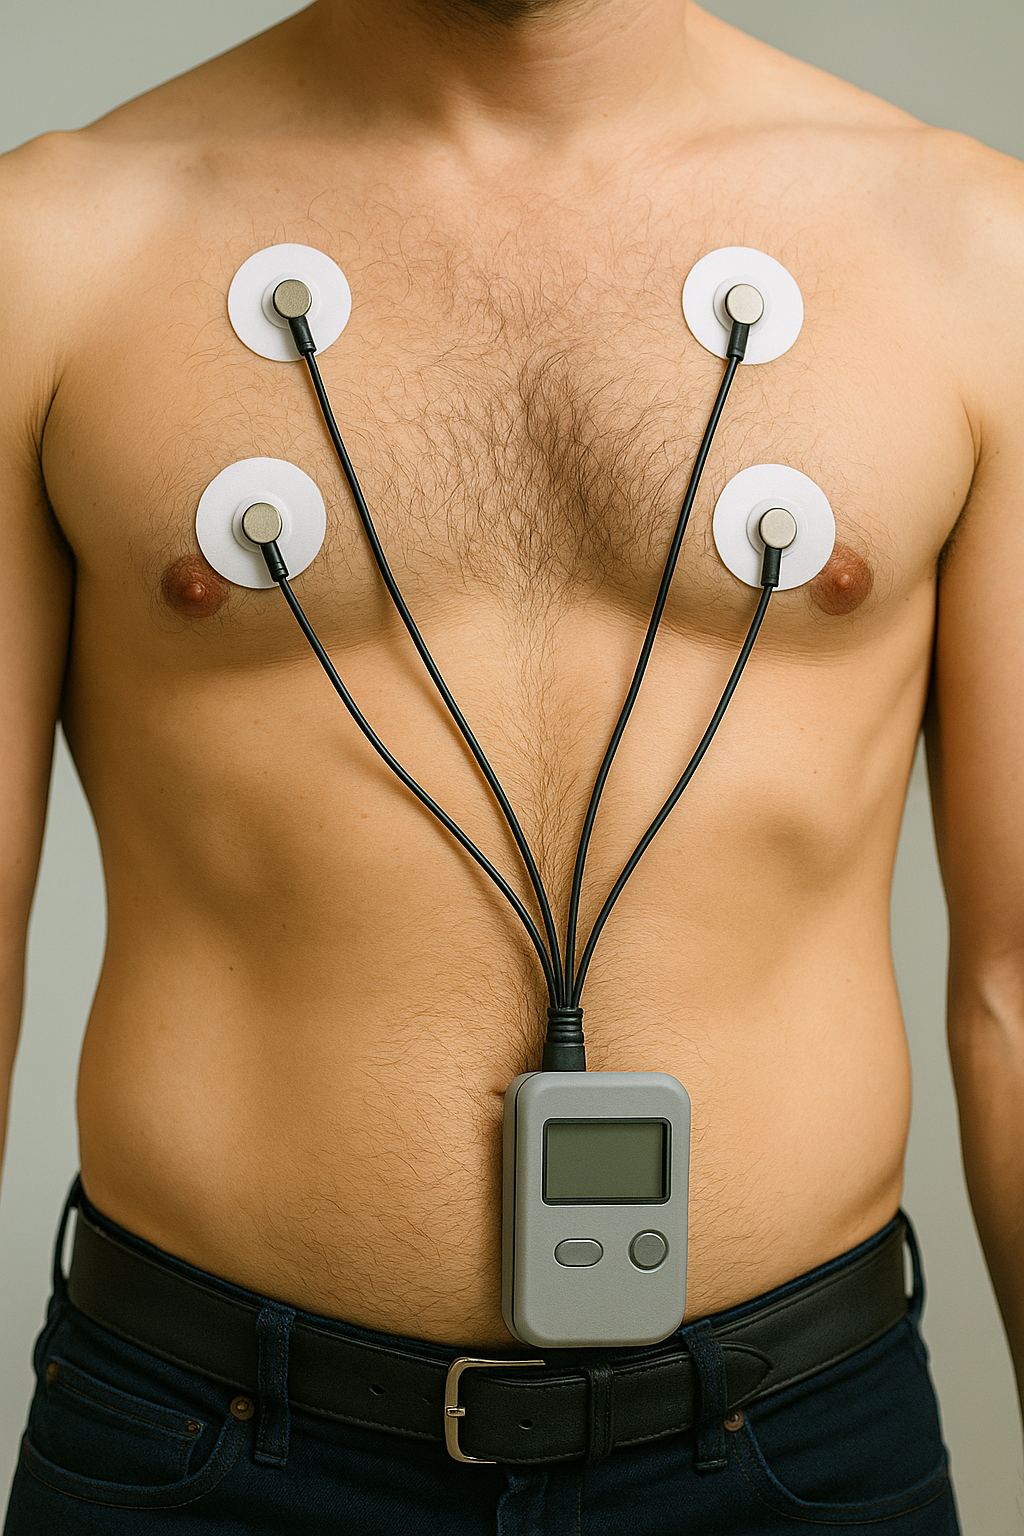

Holter Monitor

A small, portable heart monitor worn for 24–48 hours (or longer) to continuously record your heart rhythm during normal activities. Uses chest stickers connected to a recorder; painless and noninvasive.